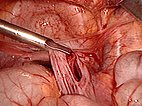

Das Peritoneum zur Bauchhinterwand wird eröffnet und alle Zysten schrittweise aus der Umgebung ausgelöst und entfernt.

Intraabdominelle retroperitoneale lymphatische Malformationen lassen sich häufig primär chirurgisch, entweder komplett oder weitgehend entfernen, mit Hilfe der minimalinvasiven laparoskopischen Chirurgie. Beide gezeigten Fälle sind bis jetzt rezidiv-frei.